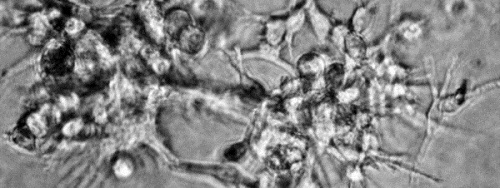

Per aquest motiu Esteller, professor d’investigació Icrea i director del Programa d’Epigenètica i Biologia del Càncer de l’Institut d’Investigacions Biomèdiques de Bellvitge (IDIBELL) i el seu equip s’han centrat en l’estudi del melanoma. Han comparat mostres de tumors primaris de pacients amb mostres de les metàstasis d’aquests mateixos pacients i és així com han aconseguit identificar una alteració en un gen. “Es tracta d’un gen, anomenat TBC1D16, que estava ‘adormit’ o no actiu i que en despertar obre la porta a la metàstasi”, indica Esteller, que afegeix que “és com una bombeta que en encendre guia a les cèl·lules canceroses del tumor primari perquè puguin escapar del seu lloc de naixement “.

Aquest ‘gen dorment’ es troba inactivat en tot l’organisme, a excepció d’un tipus de neurones i algunes cèl·lules mare en les que pel que sembla regula vies de senyalització intracel·lular: quan arriba un senyal exterior, com si fos un guàrdia de seguretat, s’encarrega d’introduir en la cèl·lula. En el cas dels tumors de melanoma, els investigadors han vist que aquest gen s’encarrega d’activar 02:00 oncogens, BRAF i EGFR, el que provoca que la cèl·lula sana es converteixi en maligna i acabi provocant aquesta disseminació en altres òrgans.

El per què s’activa aquest gen ‘dorment’ es desconeix, però aquest equip de científics han observat que en els tumors primaris està inactivat i, de sobte, en unes poques cèl·lules comença a activar-se.